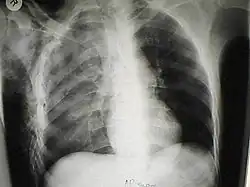

La laceración pulmonar puede no ser visible utilizando radiografía de tórax porque una contusión pulmonar asociada o hemorragia lo puede ocultar. Cuando la contusión pulmonar aclara (normalmente dentro dos a cuatro días), las laceraciones comienzan a ser visibles en la radiografía de tórax.[14] Una TAC es mejor detectando laceraciones pulmonares que una radiografía de tórax,[15] y a menudo revelan múltiples laceraciones en casos donde radiografía de pecho mostró solo un contusión. Antes de que las TAC estuvieran disponibles masivamente, la laceración pulmonar era considerada poco usual debido a que no era común encontrarlas en las radiografías. En una TAC las laceraciones pulmonares aparecen en un área contusa del pulmón,[16] típicamente apareciendo como las cavidades llenas de aire o fluido[17] que normalmente tener una forma circular u ovoide debido a la elasticidad del pulmón.

Los hematomas aparecen encima de las radiografías de tórax como masas suavizadas que son redondas u ovoide en forma. Como las laceraciones, los hematomas inicialmente pueden estar ocultos en las radiografía por contusiones en el pulmón, pero aparecen más aparentes a medida que la contusión mejora. Los neumatoceles tienen una forma similar a la de los hematomas pero tener paredes delgadas.[18] Las laceraciones pueden ser llenadas completamente con sangre, completamente con aire, o parcialmente con ambos. Las laceraciones que contienen sangre y aire muestran un distintivo nivel de aire-fluido. Una sola laceración puede ocurrir por sí misma, o también pueden existir muchas presentes, creando un aspecto como queso suizo en la radiografía del pulmón.